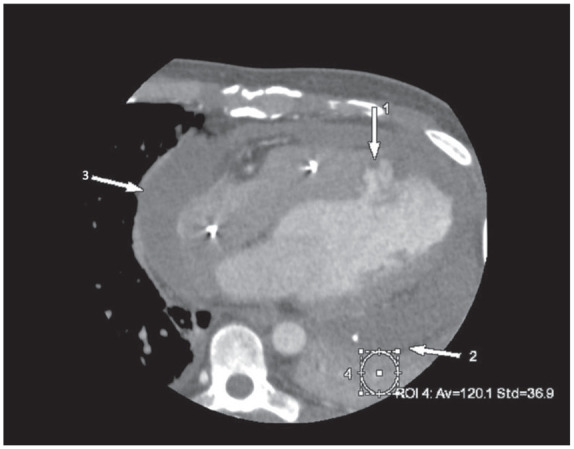

假性动脉瘤是心肌梗死(MI)的一种罕见但致命的并发症。随着心血管疾病检测和治疗技术的进步,心肌梗死后致命的结构性并发症现在已经很少见了。一旦发生,先进的诊断方法可用于早期诊断,帮助制定手术计划并改善预后。在我们的病例中,心脏计算机断层扫描血管造影术(CCTA)诊断出了心肌梗死后左心室假性动脉瘤并发血心包。CCTA 的衰减测量有助于诊断血心包的活动性外渗。该病例强调了对心肌梗死后罕见但致命的并发症需要高度怀疑,以及 CCTA 在治疗中的作用。

Pseudoaneurysm is a rare but fatal complication of myocardial infarction (MI). With the advances in cardiovascular disease detection and treatments, fatal structural complications post-MI are now rare. When they occur, advanced diagnostic modalities can be used for early diagnosis, aiding surgical planning, and improving prognosis. In our case, post-MI left ventricle pseudoaneurysm complicated by hemopericardium was diagnosed using cardiac computed tomography angiography (CCTA). Use of attenuation measurement on CCTA helped diagnose active extravasation into the hemopericardium. This case highlights the high index of suspicion needed for rare but fatal complications post-MI and the utility of CCTA in their management.